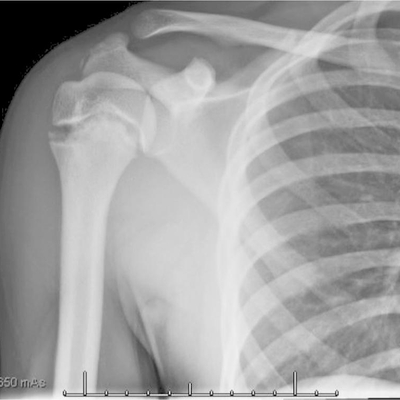

Click on an image below to view more info.